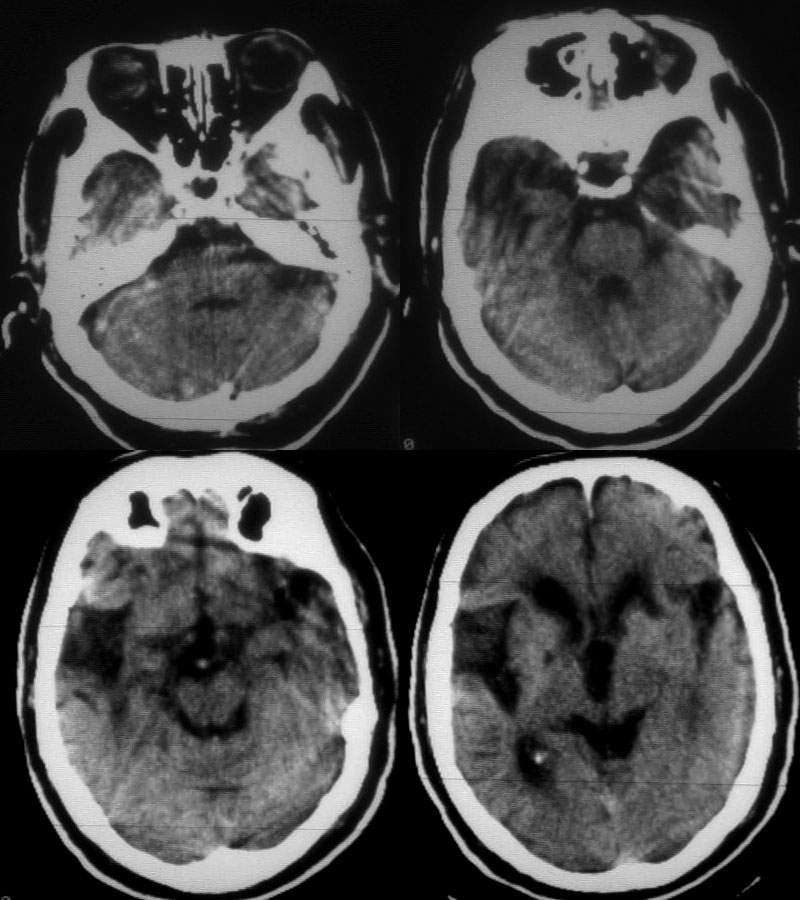

男72岁突然昏迷10小时,既往有脑梗塞病史10余年。左侧大脑梗塞?

1:右基底节区腔隙性脑梗塞

2:皮层下动脉硬化性脑病、脑萎缩(髓质型)。

老年性三联症(多发腔隙性脑梗塞 脱髓鞘变性 脑萎缩)。

1)老年性三联症(多发腔隙性脑梗塞 脱髓鞘变性 脑萎缩)。

2)除此之外,发现左侧大脑半球密度略低于右侧,脑回脑沟略变细变浅,轻度占位性改变,同侧侧脑室较对侧略窄,再者结合病人病逝,昏迷10小,我觉得24小时后复查ct以出外左侧大脑中动脉脑梗塞。

老年脑,软化灶,左侧 新鲜梗塞。(密度低,周边模糊)